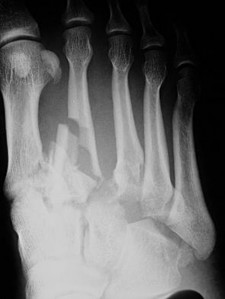

A 35-year-old female sustains a midfoot sprain. Weight-bearing radiographs demonstrate subtle widening between the medial and middle cuneiforms. The true Lisfranc ligament acts as the primary stabilizer of the second tarsometatarsal joint. What are the specific anatomic attachments of the Lisfranc ligament?

Explanation

The Lisfranc ligament is an interosseous ligament that connects the lateral aspect of the medial cuneiform to the medial aspect of the base of the second metatarsal. It is the strongest and most important ligament for stabilizing the second tarsometatarsal joint. There is no direct ligamentous connection between the base of the first and second metatarsals.